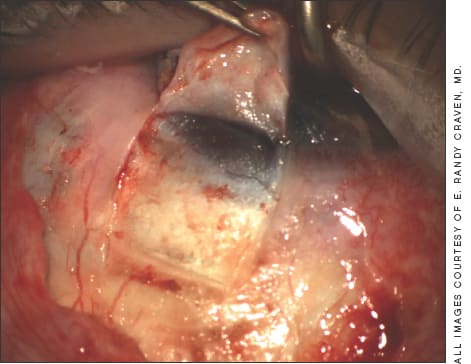

The principles of all the nonpenetrating procedures are fairly similar. First, you create an external scleral flap that will cover the deeper sclerectomy (Figure 1, previous page). Since you want the collector channels and aqueous veins to drain the aqueous, avoid excessive cautery. The shape of the scleral flap is probably best determined by what you are comfortable with and whether you think you can control the flow best by having tight closure of the flap.

Figure 1. Scleral flap created for deep sclerectomy.

I personally like to make the flap wide enough that I know I will have good closure over the inner flap. In Figure 1, the flap is about 4.5 mm wide. This outer flap is about half the thickness of the sclera.